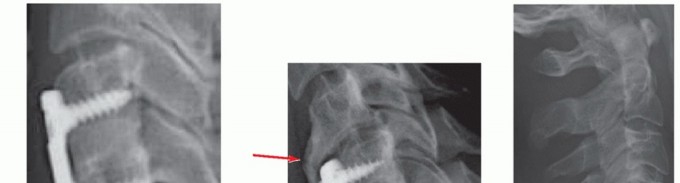

### TECH FIG 6 • Commercially available sizers are used to determine optimal graft size. A trial that fits snugly under gentle Caspar distraction will suffice. If autograft is used, the appropriate trial is used as a template for cutting the autograft bone. The surgeon should try to place a graft that fills the space as much as possible without overdistracting, which can cause posterior neck pain, or entering the spinal canal. We generally prefer to use commercially prepared cortical allografts for ACDF, except in patients with poor healing potential. Alternatively, autograft iliac crest bone can be used. ### Determining Plate Length Plating is optional for one-level ACDF with autograft. If allograft or multilevel surgery is performed, plating is recommended. Once the graft has been placed, the size of the plate is then determined. Optimal plate length is one that allows for the screws to be immediately adjacent to the endplates (TECH FIG 7). This plate length allows for screws that angle away from the disc space, which in turn allows for screws that are longer than ones directed parallel to the disc space, yet are short enough to avoid entry into the supra- and infraadjacent disc spaces. This length also prevents impingement of the plate into the adjacent disc spaces. ### Plating Techniques The plate should be contoured into lordosis to lie flush against the vertebral bodies. It should also be centered coronally within the margins of the uncinate processes. Screws should also be angled medially to decrease the chance of lateral injury to nerve roots or vertebral arteries.

### TECH FIG 7 • Proper plate sizing. A. The length of an optimally sized plate is such that the screw holes at the top and bottom of the construct are immediately adjacent to their respective endplates. In this example, even though this was done, the plate is still closer to the cephalad adjacent disc space than ideal because the vertebral bodies in this patient are relatively short. Nevertheless, adjacent-level disc degeneration did not occur in this patient at 2-year follow-up. Bicortical screw purchase is not routinely needed, but estimates of screw length can be obtained by measuring MRI or CT scans preoperatively. Screws should be angled away from the disc space to provide greater length and divergent fixation, which may better resist pullout. B. In another patient with short vertebrae who presented to us with adjacent level disease, the plate was placed too close to the adjacent disc, resulting in adjacent-level ossification disease (arrow). The cephalad screws are not immediately adjacent to the endplate but rather inserted at roughly the midpoint of the vertebral body. Similarly, the caudal screws begin in the midportion of the vertebral body. The plate is too long distally and comes close to the subjacent disc as well. As demonstrated by these examples, proper plate sizing is especially important in patients with shorter vertebrae where the adjacent discs are closer together. C. Screw fixation and graft carpentry. This patient underwent C6-C7 ACDF for cervical myeloradiculopathy. Because he had a very wide and deep disc space, two bone grafts were inserted side by side and rotated 90 degrees to the usual orientation in order to better fill the disc space, increase contact through the fusion area, and improve load sharing across the construct. Screw lengths were also optimized to improve fixation. The screw length can be estimated preoperatively by measuring the depth of the vertebral body on CT or MRI scans. Ideally, screws are as long as possible within the vertebral body to maximize fixation. Dynamic plates can be used if desired (TECH FIG 8). They have the theoretical benefit of improving load sharing on the graft. There are several types of dynamic plates. Variable screw systems allow for toggling within a fixed screw hole with settling of the construct. A potential downside is that the screw can loosen within bone as toggling occurs. Slotted plates have holes that allow screws to translate longitudinally as the construct shortens. The screws are rigidly fixed to bone and do not toggle, but excessive translation may lead to adjacent-level plate impingement. Telescoping plates use fixed screws in nonslotted holes but the ends of the plate telescope with respect to each other as settling occurs. Postoperative adjacent-level plate impingement will not occur with this design if the plate is properly positioned at the time of surgery, as the distance from the end of the plate to the endplate does not change with construct shortening. However, these plates tend to be somewhat thicker. If dynamic plates are used, the surgeon must perform the plating procedure to accommodate the anticipated settling without overlapping uninvolved adjacent discs.8 In general, we prefer rigid plating in most cases to avoid excessive construct settling. Variable plating has not been clearly demonstrated to improve outcomes or fusion rates. 8